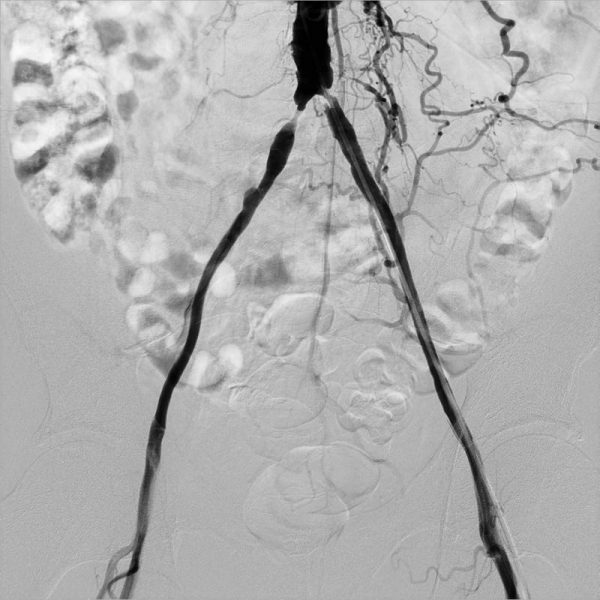

На следующем фото – момент позиционирования стентов в участках сужения.